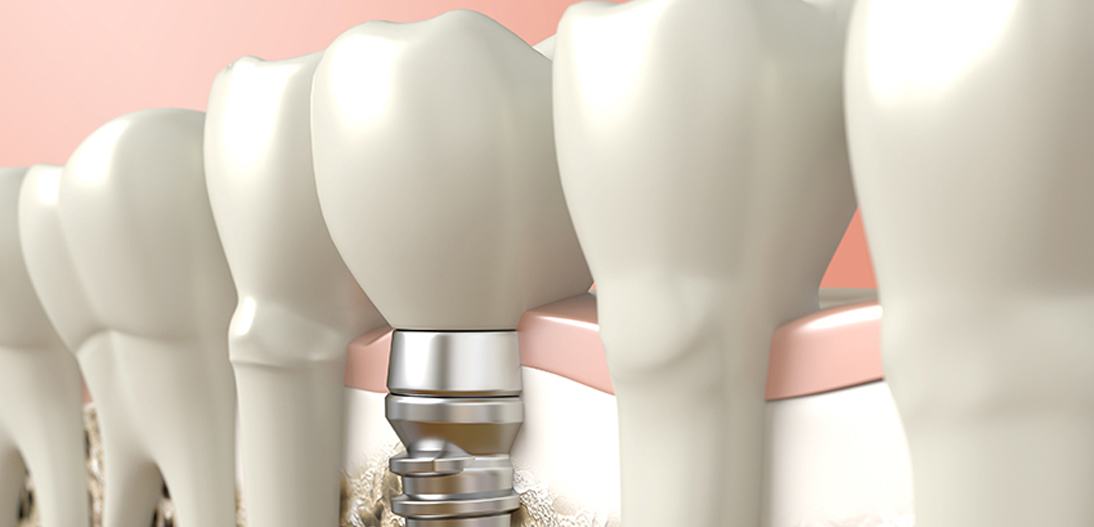

O que é implante dentário?

Implante dentário é um cilindro (pino) de titânio colocado dentro do osso, abaixo da gengiva e que tem a função de fazer o mesmo papel da raiz do dente. Em cima do implante é que o cirurgião dentista coloca o dente.